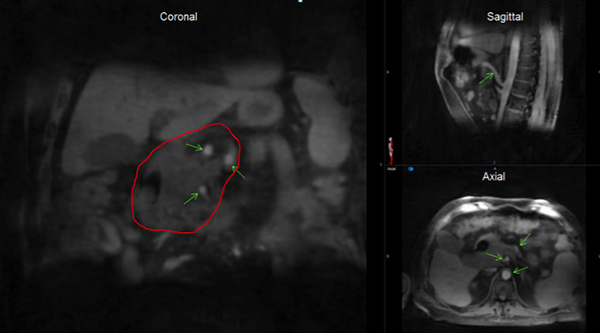

- MR guided radiation therapy for pancreas and liver stereotactic body radiation therapy (SBRT)

Novel 4-D-MRI images with high isotropic resolution, free from stitch artifacts and excellent blood vessel contrast that can be used to accurately define both pancreatic tumor and boost volume margins for SBRT with simultaneously integrated boost.

Implementing novel multi-parametric MRI for liver cancer patients showing excellent correlation of imaging-defined tumor and corresponding specimen cut. Functional MRIs resolved more heterogeneity within the tumor.